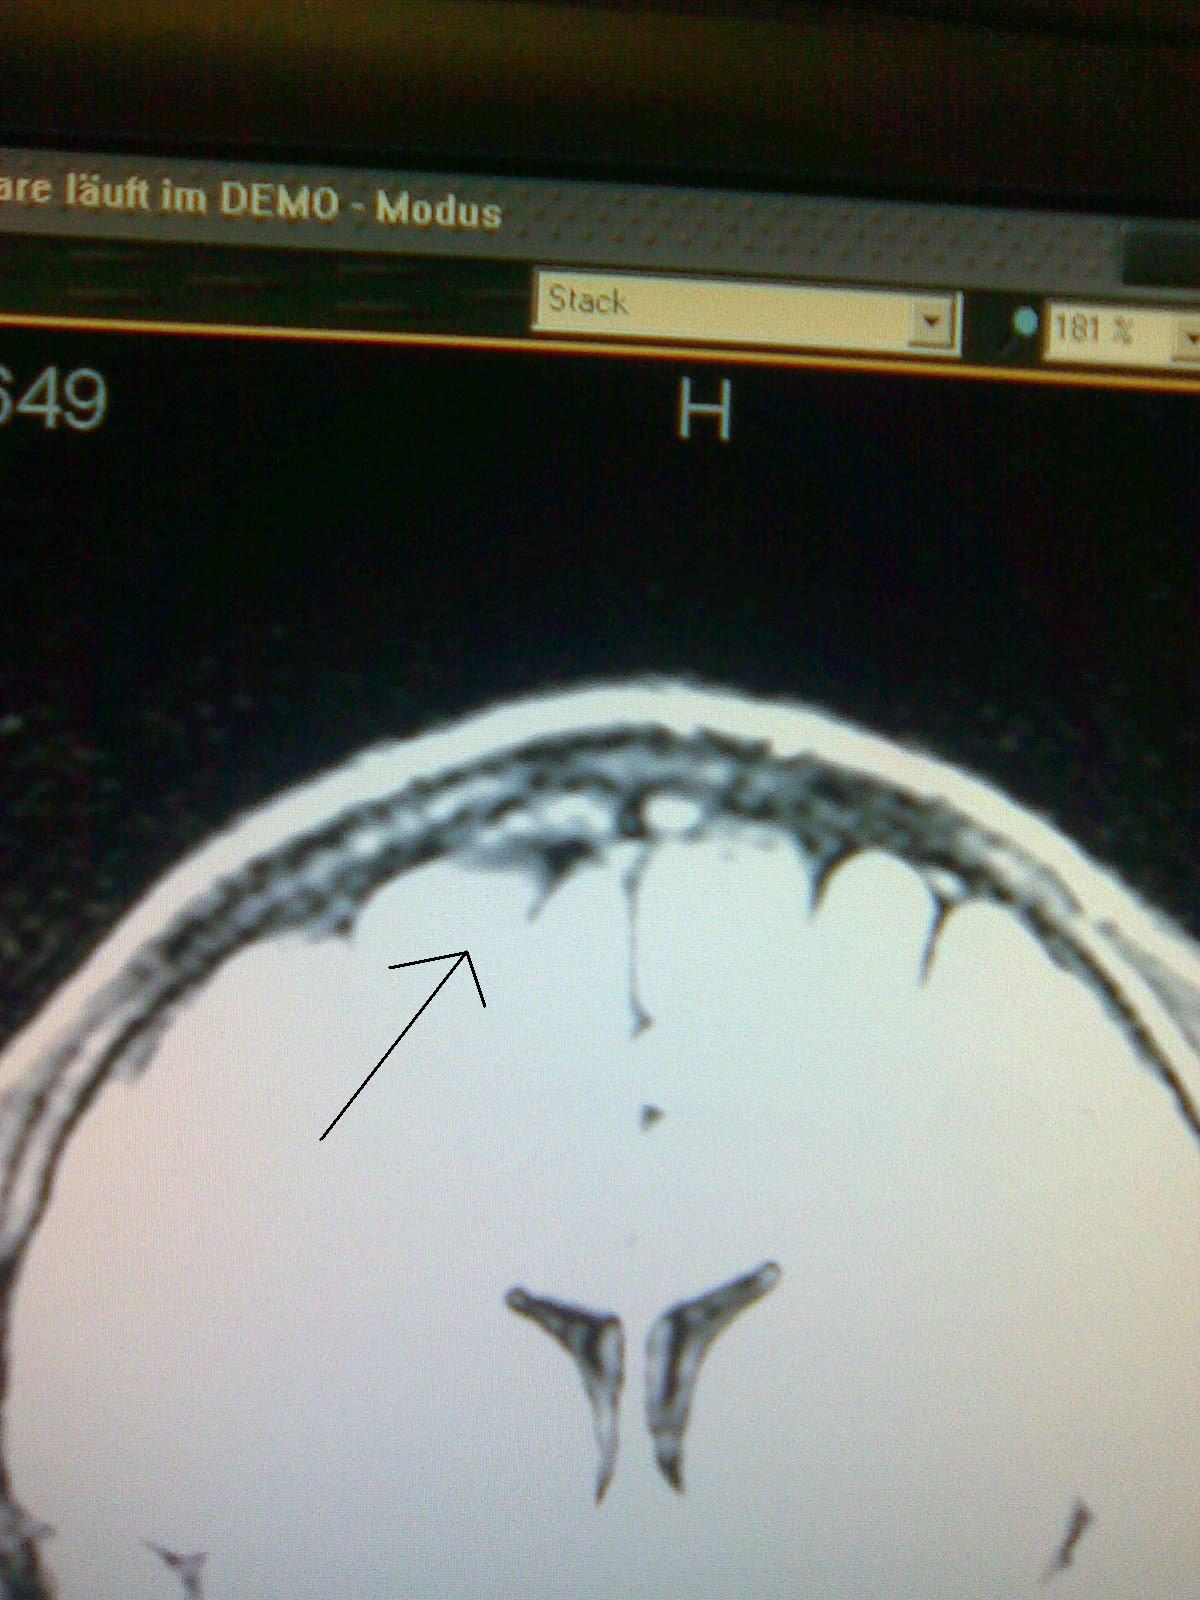

Aber normalerweise müßte schwarz eher unbedenklich eingestuft werden. Am rande vom Gehirn siehst du wohl die Hirnflüssigkeit, die eben aufgrund ihrer Dichte o.ä. dunkler dargestellt wird.

Ein Gehirn ist kein symmetrisches Gebilde, daher sieht es für mich einfach nach einer natürlichen furche oder spalte an der Außenseite in den Windungen aus. Das weiße da drüber ist wohl wieder eine Windung in einer anderen Ebene. Das Bild zeigt nur eine schicht.

Soll angeblich ne achadeulalzyste oder sowas sein....nie im leben...naja,ich habe erstmal noch son termien gemacht